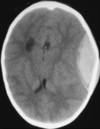

quadro súbito com vômitos ( antecedente de hipertensão) desorientada + rigidez de nuca. Neurológico normal. Devido a idade da paciente sempre pensar em hsa ( devido prsença de aneurisma sacular congênito da artéria comunicante anterior ) tc sem contraste ( veja o branco brilhante desenhando o mesencéfalo , famosa " orelinha "